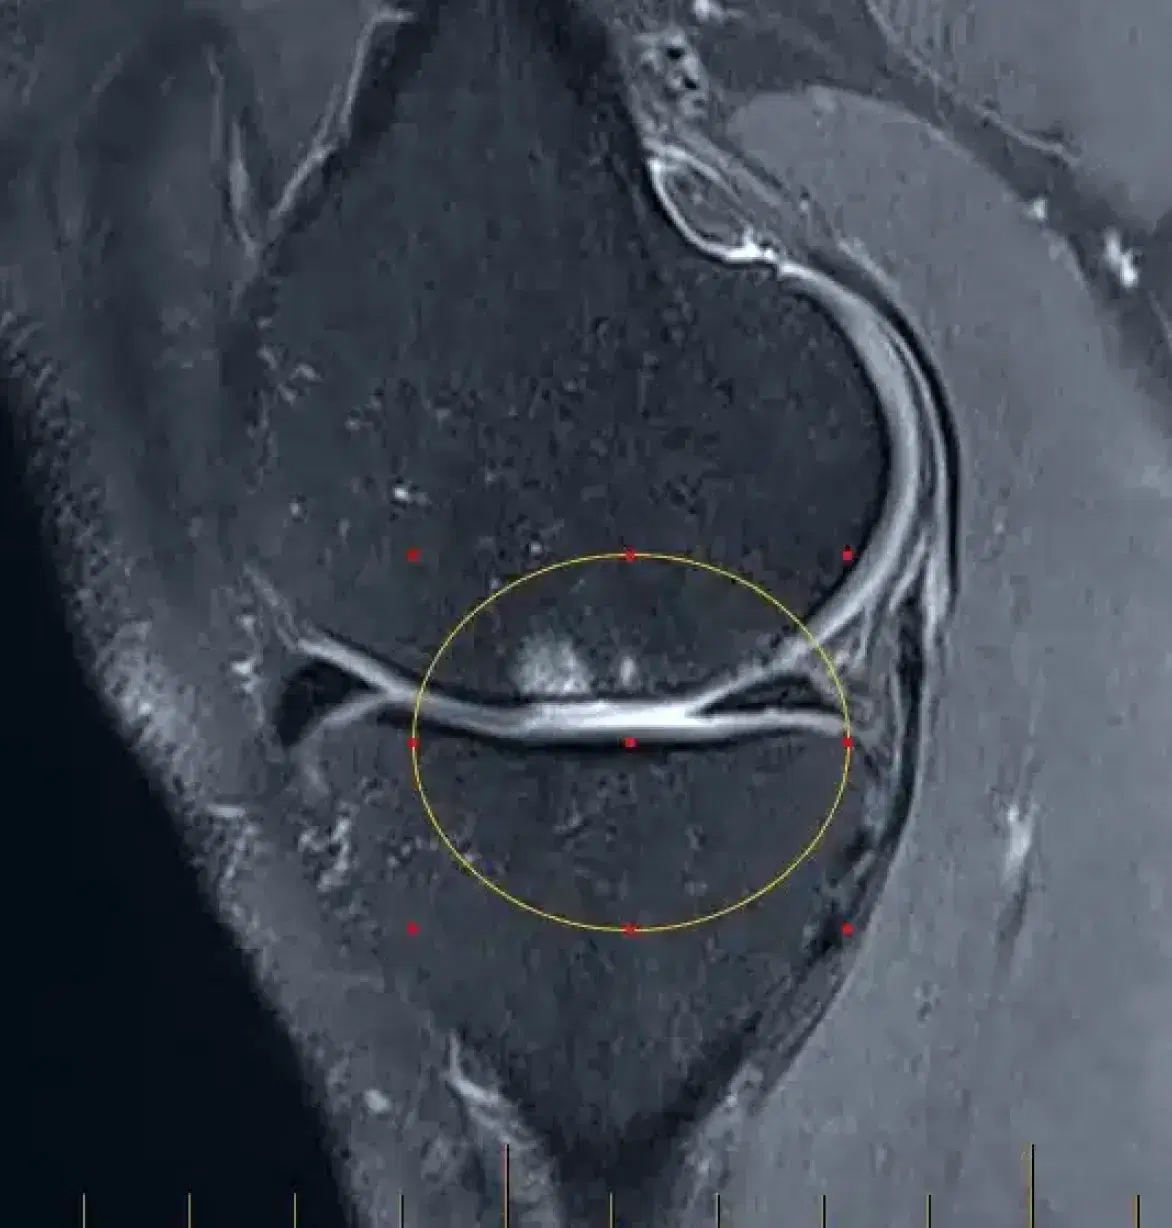

MRI scan of the left knee confirming cartilage damage to the inner side of the knee. (circled)